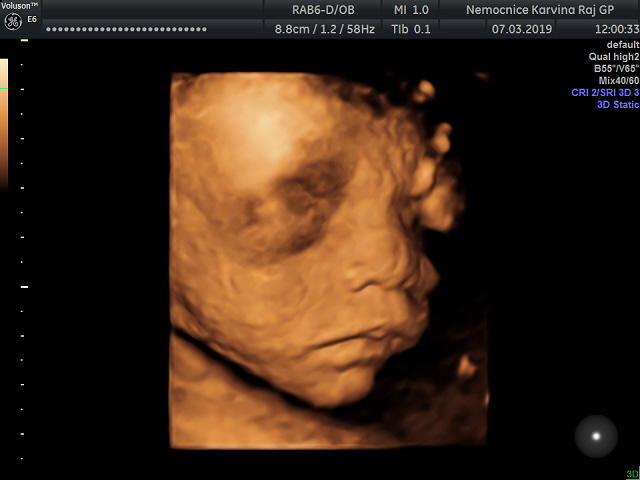

3D ultrazvuk - stojí to za to?

Stojí to za to? 🙂 Jaký jsou pak fotky? Dívala jsme se s manželem na google, jak ty fotky vypadají. A ani mě ani manželovi se ty fotky vůbec, ale vůbec nelíbí :D :-/

Nechci to nijak znevažovat, pomlouvat, rozmlouvat. To určitě ne 🙂 Miminko nám na fotkách přijde takový neforemný, nehezký. Naše miminko už teď milujeme 🙂

Věřím, že to je hezká vzpomínka na těhotenství. Změní se nám názor, až miminko na 3D uvidíme? Opravdu to stojí za to? 🙂

Dnes jsem se doktora ptala na ten 3D utz. Dělá ho on, stojí to 1500 a je to strašně nejisté, může to být za 10 minut hotový nebo tam může hodinu lovit aspoň trochu přijatelný záběr :D Ještě to promyslíme 🙂